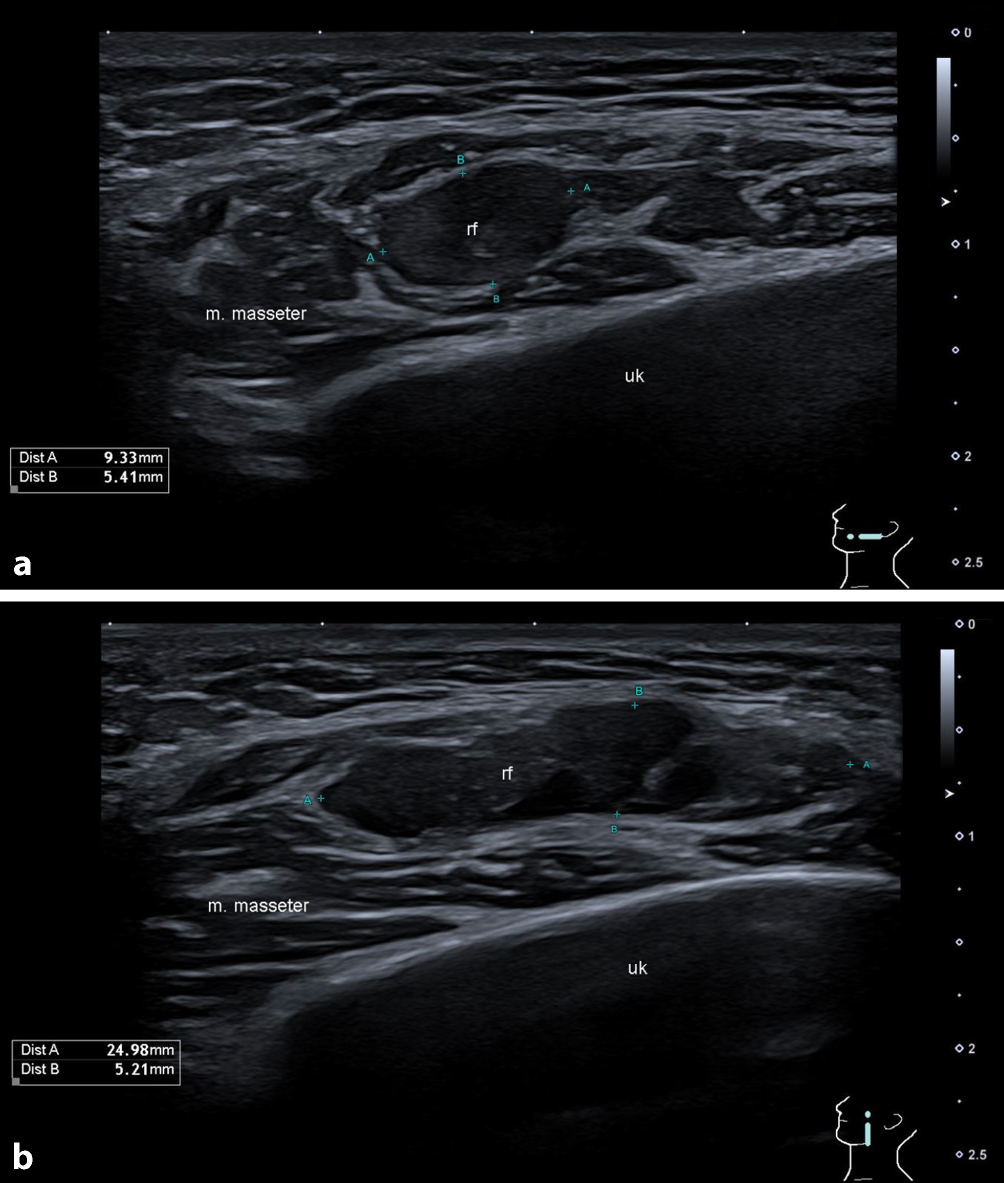

Die sonographische Kontrolle bestätigte eine 24,9 × 9,2 × 5,4 mm große, avaskuläre, inhomogene, zystische Raumforderung im linken M. masseter. Keine dorsale Schallverstärkung oder Schallschatten (Abb. 2). Zusätzlich fanden sich in den Leveln Ib und IIa links vergrößerte ovale, hilär vaskularisierte, scharf begrenzte Lymphknoten ohne Malignitätszeichen. Ein ergänzendes Orthopantomogramm (OPG) ergab keine Hinweise auf röntgendichte Fremdkörper, dentogene Foci oder anderweitige knöcherne Pathologien, die die klinischen Beschwerden erklären konnten.

Abb. 2

B‑Bild-Sonographie des Kopfes. a transversal und b longitudinal. rf Raumforderung, uk Unterkiefer, m. masseter M. masseter